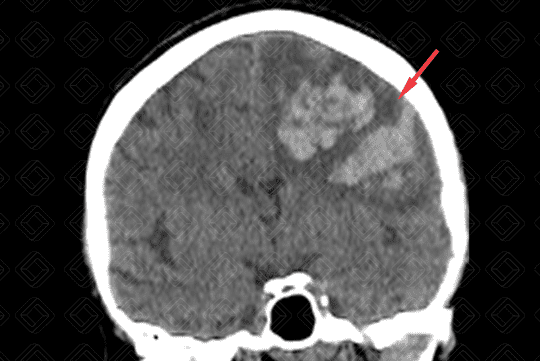

Descrição das imagens: Paciente masculino, 68 anos, com hemorragia intracraniana causada por rotura de um aneurisma da artéria cerebral média esquerda. Observa-se a presença de áreas espontaneamente densas (sangue), intraparenquimatosas, no lobo frontal e parietal esquerdos (setas vermelhas), causando discreto desvio da linha média contralateralmente. Nota-se ainda hipodensidade periférica devendo representar edema.

• Tomografia computadorizada do crânio: Deve ser feita avaliando sua densidade, seu volume, sua localização e sua relação com as estruturas circunjacentes. Lembrar que a densidade compatível com sangue na tomografia computadorizada encontra-se em torno de 50 a 70 UH. Permite ainda avaliar se há efeito compressivo ou desvio de linha média, por exemplo. A aparência da hemorragia intracraniana não complicada na tomografia computadorizada é relativamente direta e de fácil percepção (Figura 1);